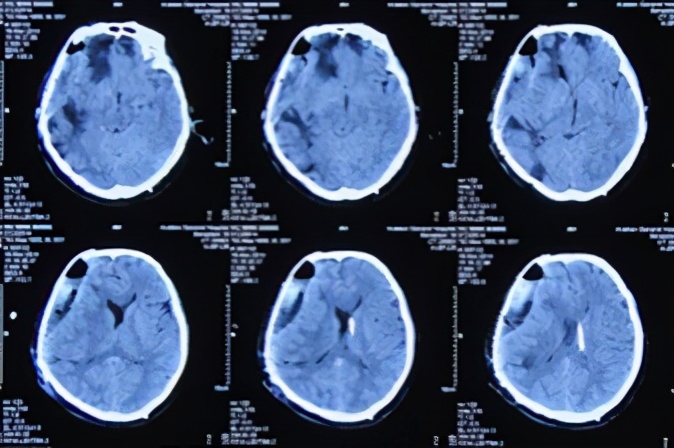

2013年10月5日即入院术后第4天(开颅术后第18天),复查头CT:脑肿胀及脑膨出均减轻(图-9)。

图-9:2013年10月5日头CT

于2013年10月7日即入院术后第6天(开颅术后第20天),再次复查头CT显示脑肿胀及脑膜脑膨出继续减轻(图-10)。并当天给予行右颞部原伤口的二次缝合术(注:彻底封闭了脑外露)(图-11)。

图-10:2013年10月7日头CT

2013年10月13日即入院术后第12天(开颅术后第26天),再次复查头CT:脑肿胀及脑膨出进一步减轻(图-12)。

图-12:2013年10月13日头CT

2013年10月27日即入院术后第26天(开颅术后第40天),但间断叙述头痛并夜间躁动不安,当晚复查头颅CT:脑膨出、脑肿胀进一步改善(图-13)。

图-13:2013年10月27日头CT